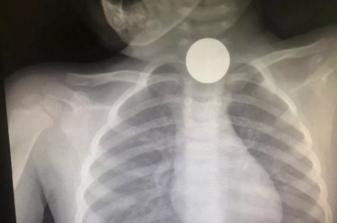

(一枚硬币卡在食管上端)

近日,家住宁波鄞州的2岁小女孩妞妞,在误吞硬币3天后才被家长发现异常,送到宁波浙江大学明州医院儿科检查时,妞妞的食管已出现溃疡,并有食管穿孔。

2岁女孩误吞硬币 引起食管穿孔

“据家长描述,患儿近2天饭量明显变少,抗拒吃东西,一吃就吐就哭,他们以为是咽喉炎之类的便决定观察看看。”施主任说,“看到情况一直不好转,就送来医院检查,结果拍片提示在食管上端卡着一枚硬币。”

由于妞妞有食管穿孔,在取出硬币后,通过鼻饲吃了两个礼拜牛奶,复查食管已经恢复如常,妞妞才恢复了正常饮食。